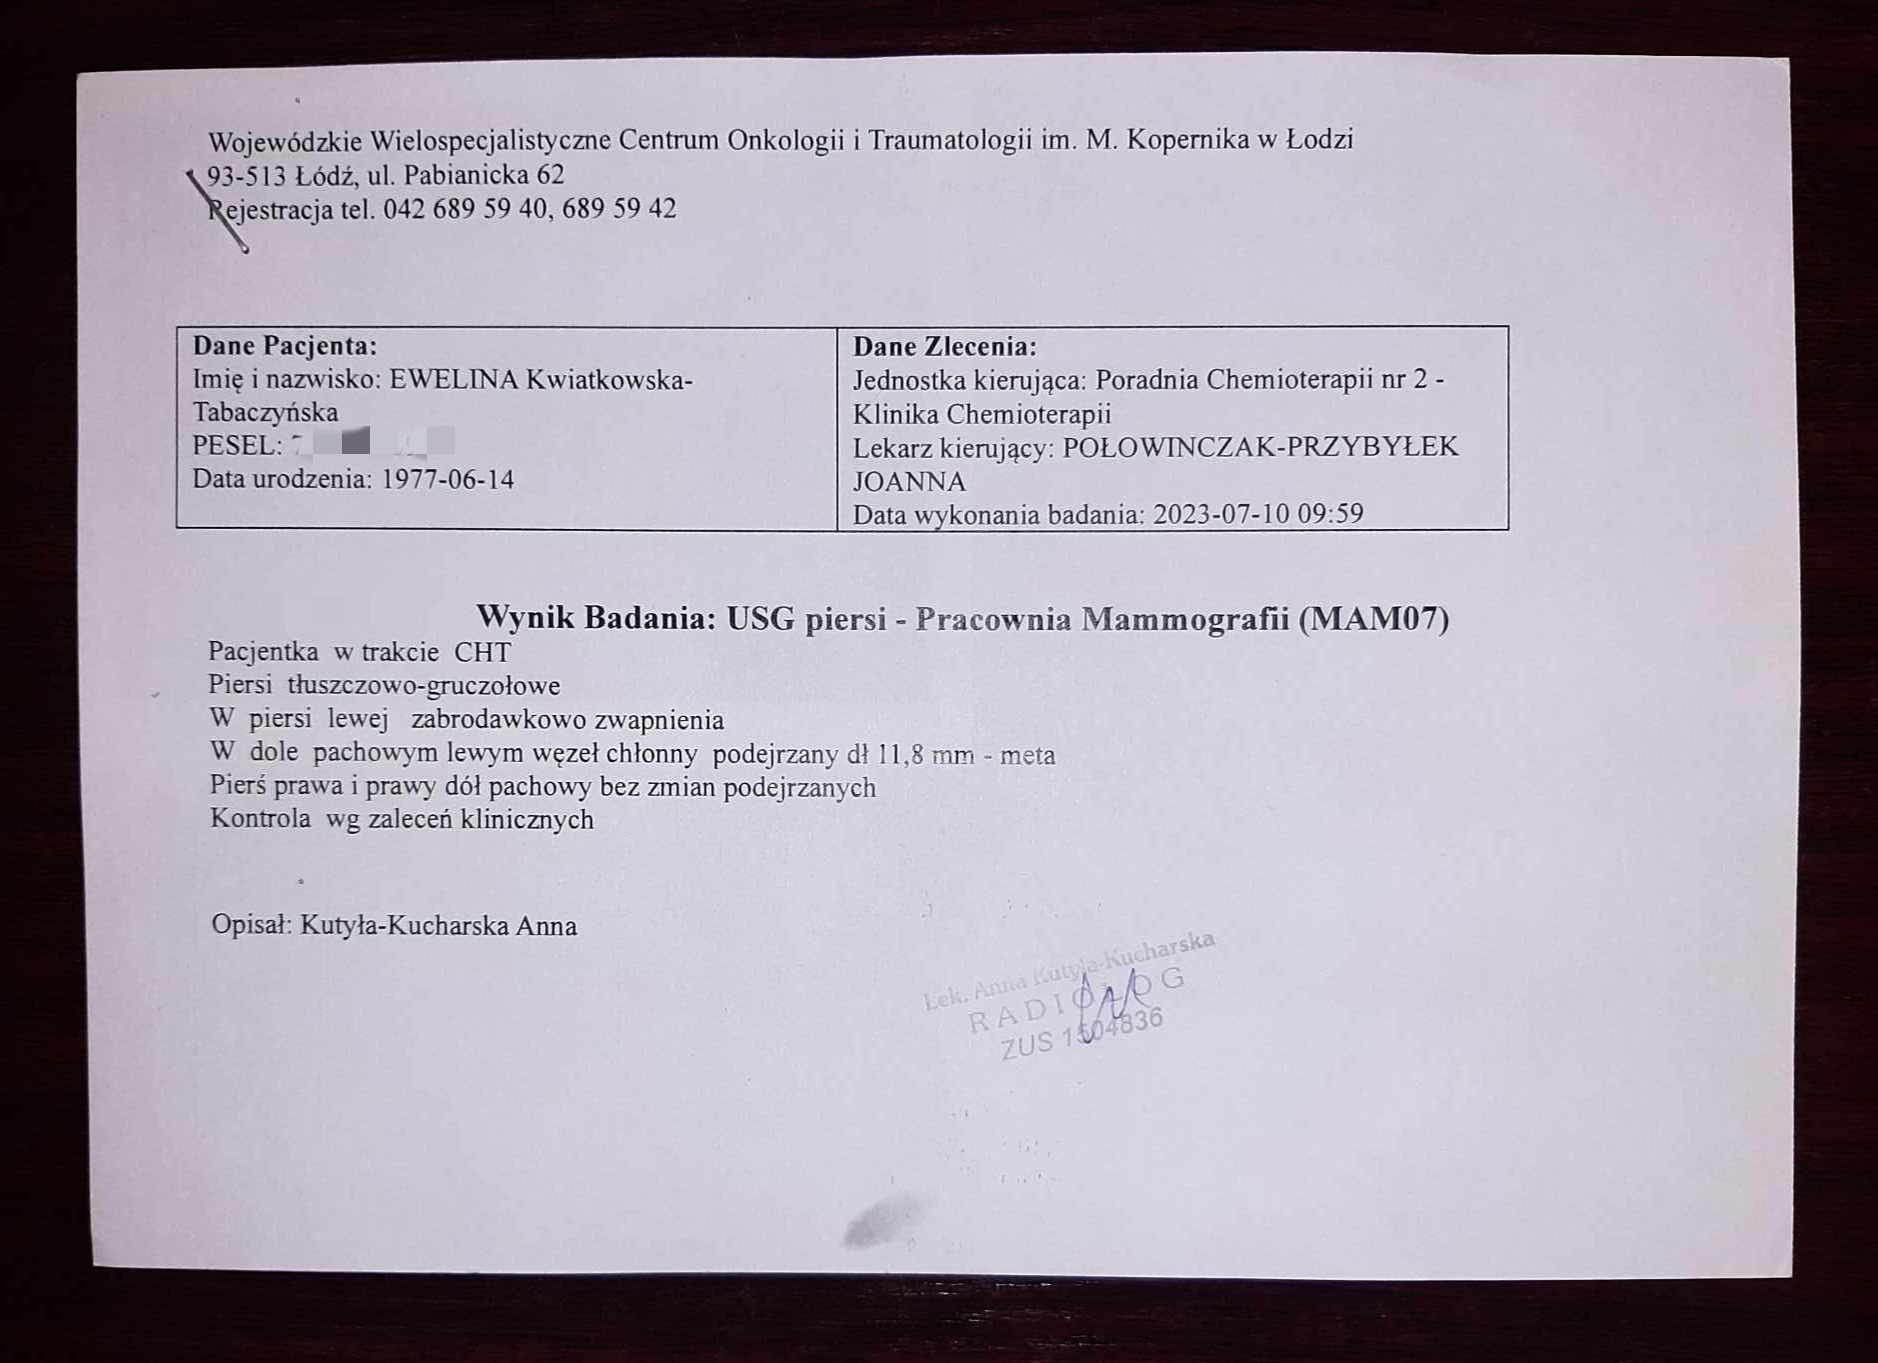

Regularnie co trzy miesiące mam wykonywane wszystkie badania kontrolne w ramach programu lekowego i prowadzonym leczeniem rybocyklibem. Mamy już wyniki usg piersi z dnia 10.07.2023. i wynik usg jamy brzusznej (wyniki poniżej w formie zdjęć), czekamy na wynik scyntografii kości i rtg klatki piersiowej.